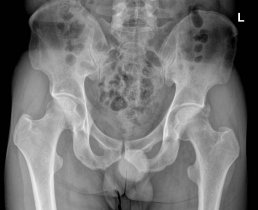

¹æ»ç¼± °Ë»ç :  ÁÂÃø °í°üÀý  ¿ÜÃø ¿Í¼ø°ú °üÀý³¶ºÎÀ§  ¼®È¸È­(+)(»çÁø10) * »çÁøÀ» Ŭ¸¯Çϸé ÇØ´ç »çÁøÀÌ º¸ÀÔ´Ï´Ù.

5ÁÖ ÈÄ  ÃßÀû°Ë»ç ¹æ»ó¼± °Ë»ç¿¡¼­ ¼®È¸°¡ °ÅÀÇ ¿ÏÀü ¼Ò½Ç µÊ(»çÁø 11)..